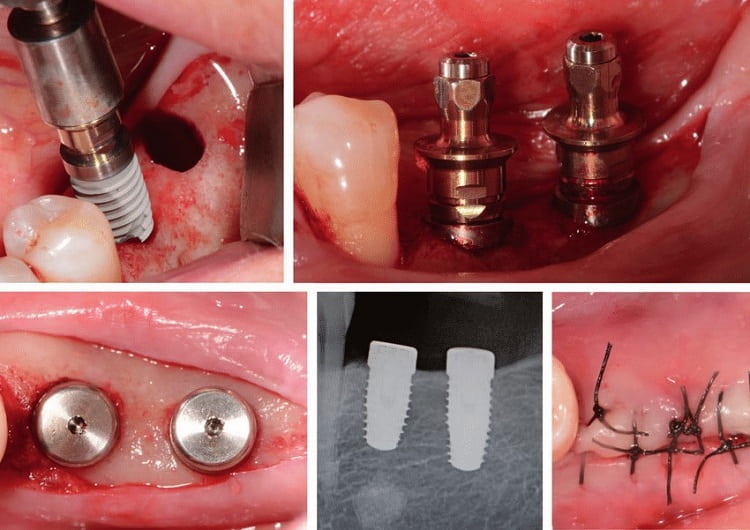

قرار دادن ایمپلنت دندان

در طی جراحی به منظور قرار دادن کاشت دندان، جراح دهان و دندان یک برش برای باز کردن لثه و رسیدن به استخوان ایجاد می کند. در درون استخوان حفره هایی ایجاد می شود تا پست (پایه) ایمپلنت در آن قرار گیرد. از آنجایی که پایه نقش ریشه دندان را بازی می کند، باید در عمق استخوان قرار بگیرد.

در این مرحله، در جایی که دندان خود را از دست داده اید هنوز فضای خالی دارید. در صورت نیاز، می توان نوعی پروتز موقتی و جزئی برای حفظ ظاهر قرار داد. می توانید در هنگام شستشوی دهان و خواب آن را بردارید.

صبر کردن برای رشد استخوان

زمانی که پایه فلزی ایمپلنت در استخوان فک قرار گرفت، ادغام استخوان و ایمپلنت آغاز می شود. در طی این فرآیند، استخوان فک رشد می کند و با سطح ایمپلنت دندانی ترکیب می شود. این فرآیند که می تواند چندین ماه زمان برد، به ایجاد پایه محکم برای دندان مصنوعی جدید کمک کرده و همانند ریشه های دندان اصلی عمل می کند.

قرارداردن اباتمنت / بدنه

وقتی ادغام استخوان و کاشت کامل شد، ممکن است نیاز به جراحی بیشتر برای قرار دادن بدنه داشته باشید، بدنه قسمتی است که تاج در نهایت روی آن متصل می شود. این جراحی کوچک معمولاً با بی حسی موضعی و در بخش سرپایی انجام می شود.

برای قرار دادن اباتمنت:

- جراح دهان و دندان لثه را مجدداً باز می کند تا به ایمپلنت برسد.

- اباتمنت به ایمپلنت متصل می گردد.

- سپس بافت لثه در اطراف اباتمنت بسته می شود اما در روی آن باز می ماند.

در مواردی، اباتمنت به پایه فلزی ایمپلنت دندانی و در جایی که پایه قرار گرفته شده متصل می شود که یعنی نیازی به جراحی اضافه ندارید. زیرا اباتمنت فقط از خط لثه کمی بالاتر است. هر زمان که دهان خود را باز می کنید قابل مشاهده است و تا زمانی که دندانپزشک پروتز دندان را کامل کند همانگونه باقی خواهد ماند. برخی این حالت را دوست ندارند و ترجیح می دهند که اباتمنت در مرحله ای جداگانه متصل گردد.

بعد از اینکه اباتمنت قرار گرفت، قبل از اتصال دندان مصنوعی، در عرض دو هفته، لثه باید ترمیم گردد.

بعد از هر مرحله جراحی، ممکن است تا زمان ترمیم محل جراحی، نیاز به خوردن غذاهای نرم داشته باشید. معمولاً، جراح بخیه هایی استفاده می کند که خود به خود جذب می شوند. اگر بخیه ها جذبی نبودند، پزشک آنها را می کشد.